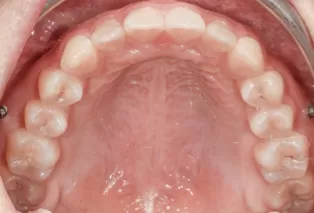

Photos intra-orales

teeth straightening aligners 4

teeth straightening aligners 5

teeth straightening aligners 6

teeth straightening aligners 7

teeth straightening aligners 8